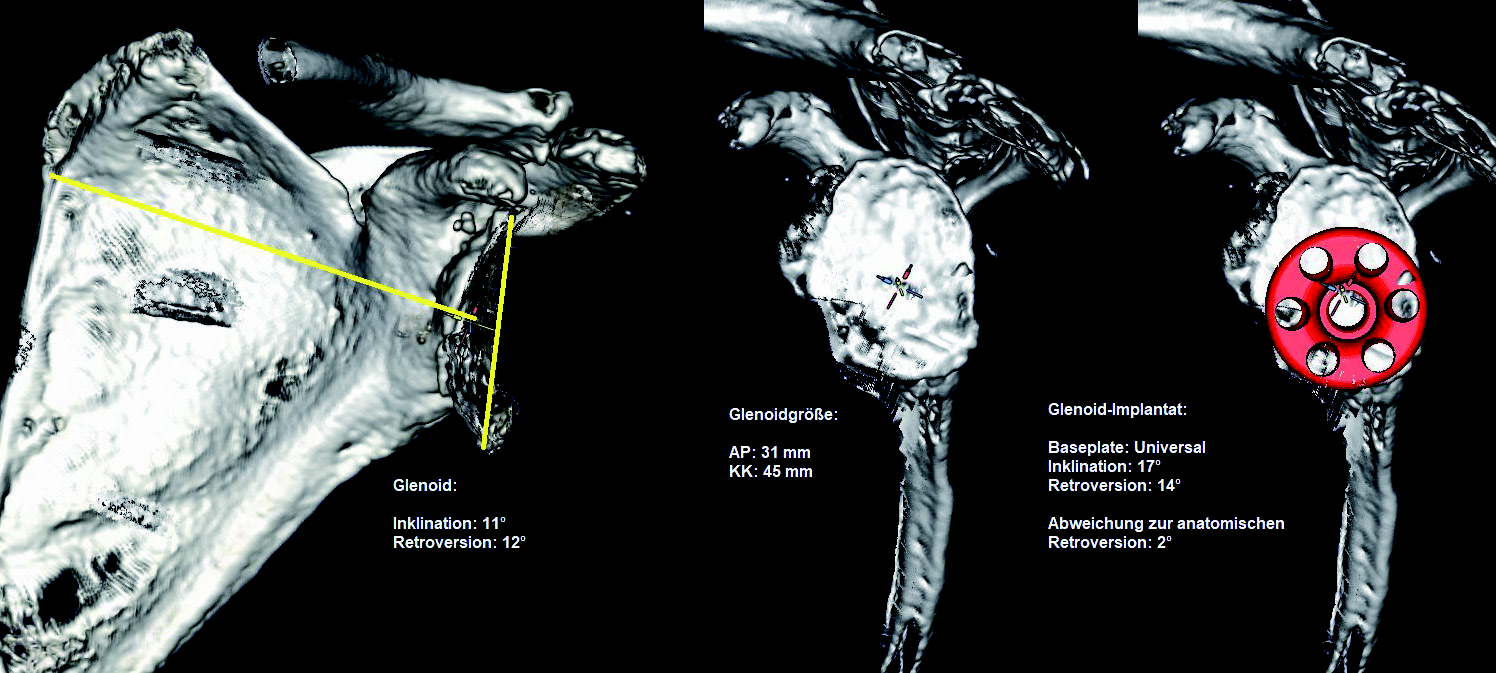

For every upcoming surgery, I try to make at least one digital 2D plan, ideally even a 3D plan.

even a 3D plan. However, 3D planning is based on CT images, and unfortunately I do not always have a suitable CT with the appropriate thin-slice resolution and dimensions (entire scapula and epicondyles), because many patients only have an MRI with them, which usually does not show the end points of the affected bones that are actually required, and they assume that this is sufficient.

and assume that this is sufficient. However, digital 2D planning is also possible on the basis of an

MRI, but with significantly more limited information than 3D planning with reproducible reference planes in the scapula planes and humeral axes.

Correct implant positioning has a significant impact on postoperative functional outcomes, from

instability, wear, and secondary soft tissue problems with rotator cuff lesions to prosthesis failure with prosthesis loosening. For this reason, preoperative prosthesis planning is essential. The pure

two-dimensional planning on the conventional X-ray is not sufficient for the shoulder. For exact positioning, three-dimensional planning based on CT data, with standardized reference planes as the starting position for reproducible planning, offers a good possibility that extends to preoperative dynamic simulation.